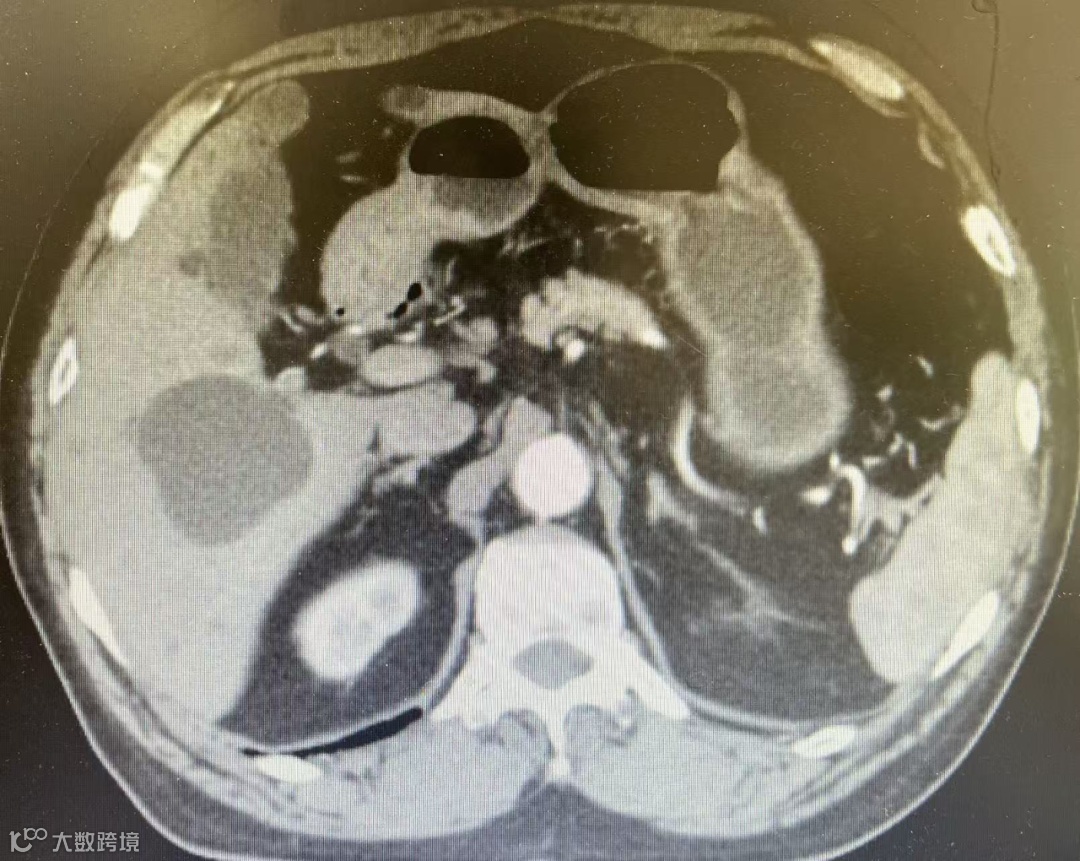

术前,科室团队结合患者影像资料进行了细致评估,精准规划了穿刺路径。术中在CT实时引导下,穿刺针准确抵达目标位置,成功抽吸囊液并完成冲洗。随后,经造影确认位置无误后,注入硬化剂并保留。术后复查显示囊肿已基本消失,手术取得预期效果。整个流程平稳有序,以微创方式为患者解除了病痛。

CT引导下硬化治疗

相较于传统的开腹或腹腔镜囊肿开窗术,CT引导下聚桂醇硬化治疗有着显著的临床优势。